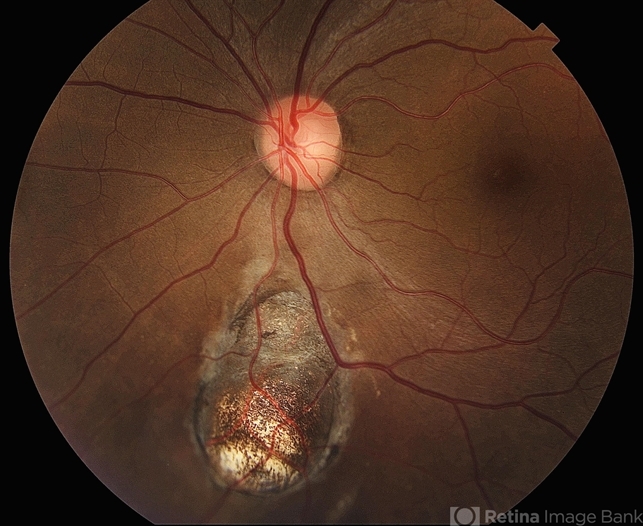

- Retinal Coloboma found in a female 41 year old patient. Iris, Lens, Ciliary Body, Zonules, Choroid and Retina were involved.